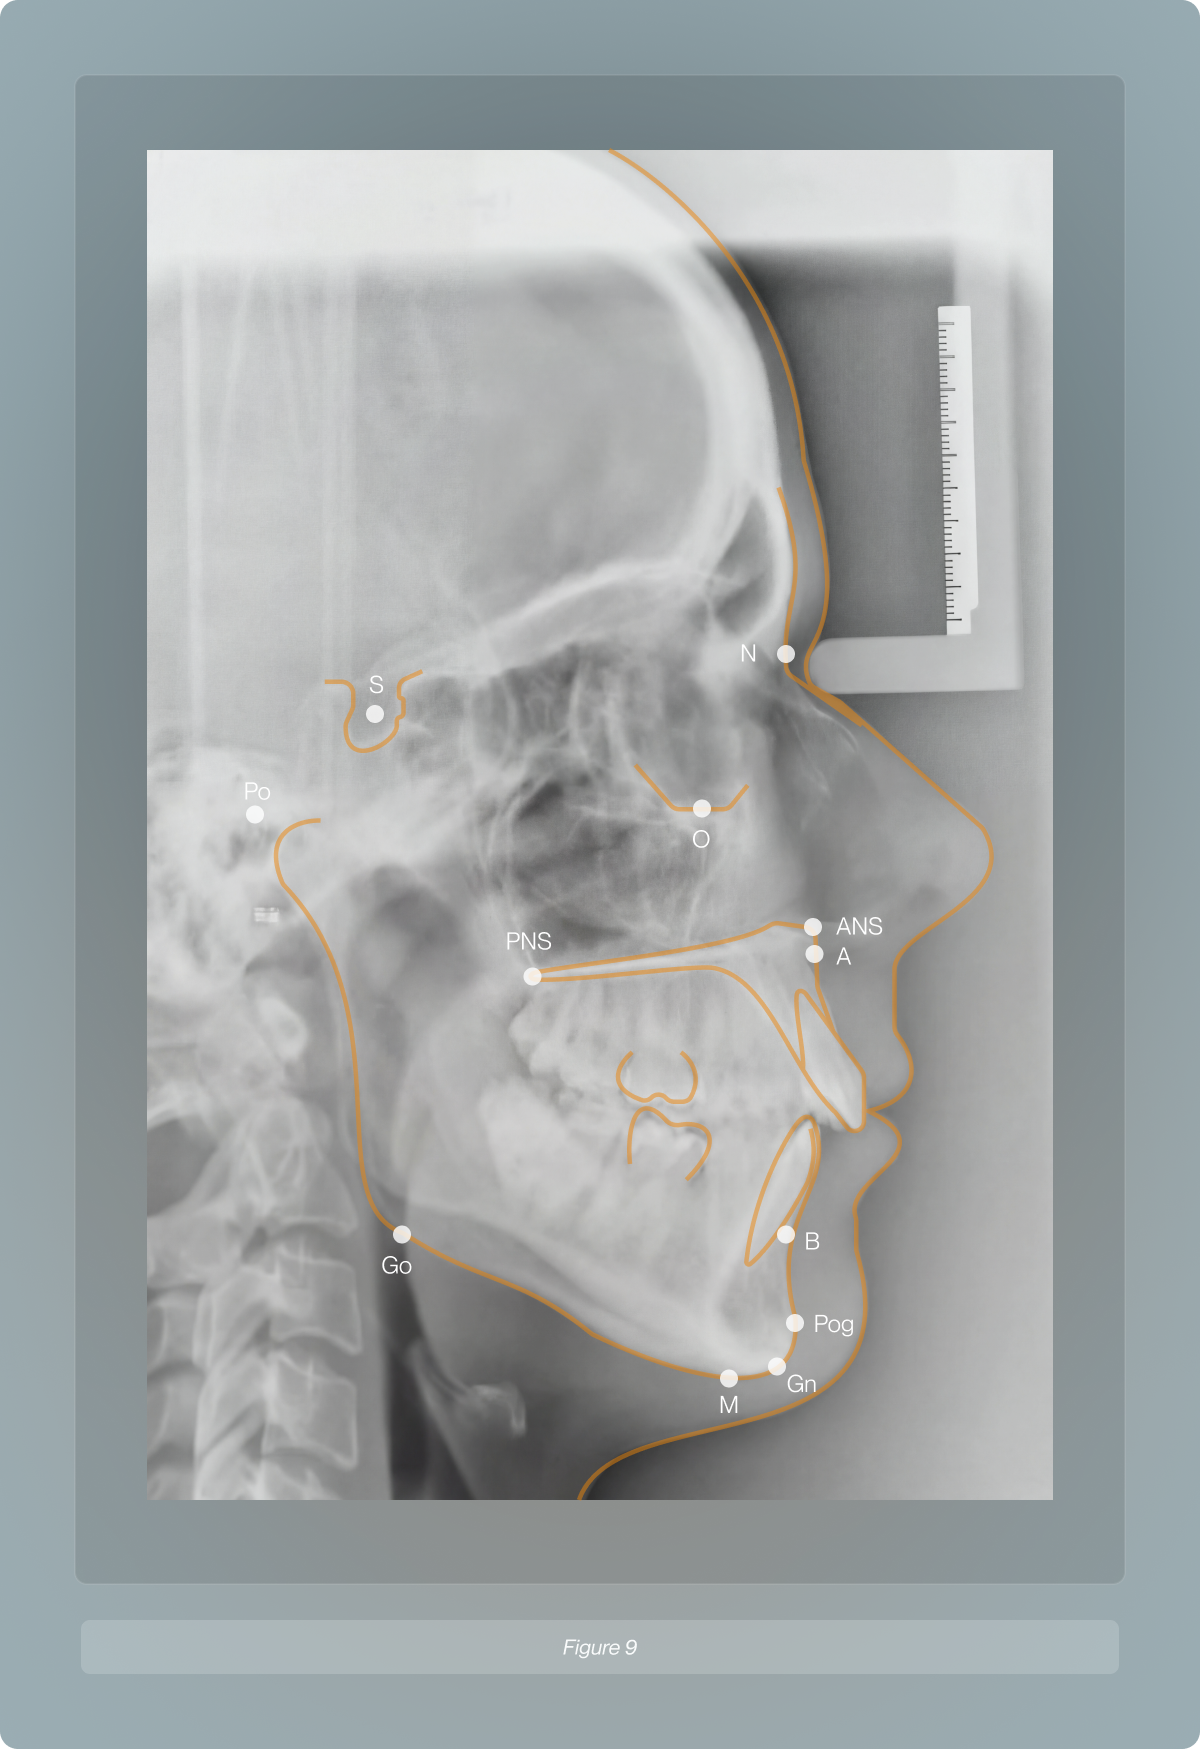

Two parallel technologies drove this shift. First, cephalometrics, which standardised lateral skull radiographs, were introduced into orthodontics34,35. Cephalometric analyses use skeletal landmarks (e.g., sella, nasion, A-point, B-point) to generate angular and linear measurements such as SNA, SNB, ANB, and mandibular plane angle.

Lateral cephalometric radiograph with traced skeletal and soft tissue landmarks, used to assess craniofacial proportionality beyond surface-level measurements.

These values are compared with population means and standard deviations, often stratified by sex and age, to diagnose skeletal discrepancies and plan growth-modifying or orthognathic treatments36. Instead of one “ideal” profile, cephalometrics offers ranges.